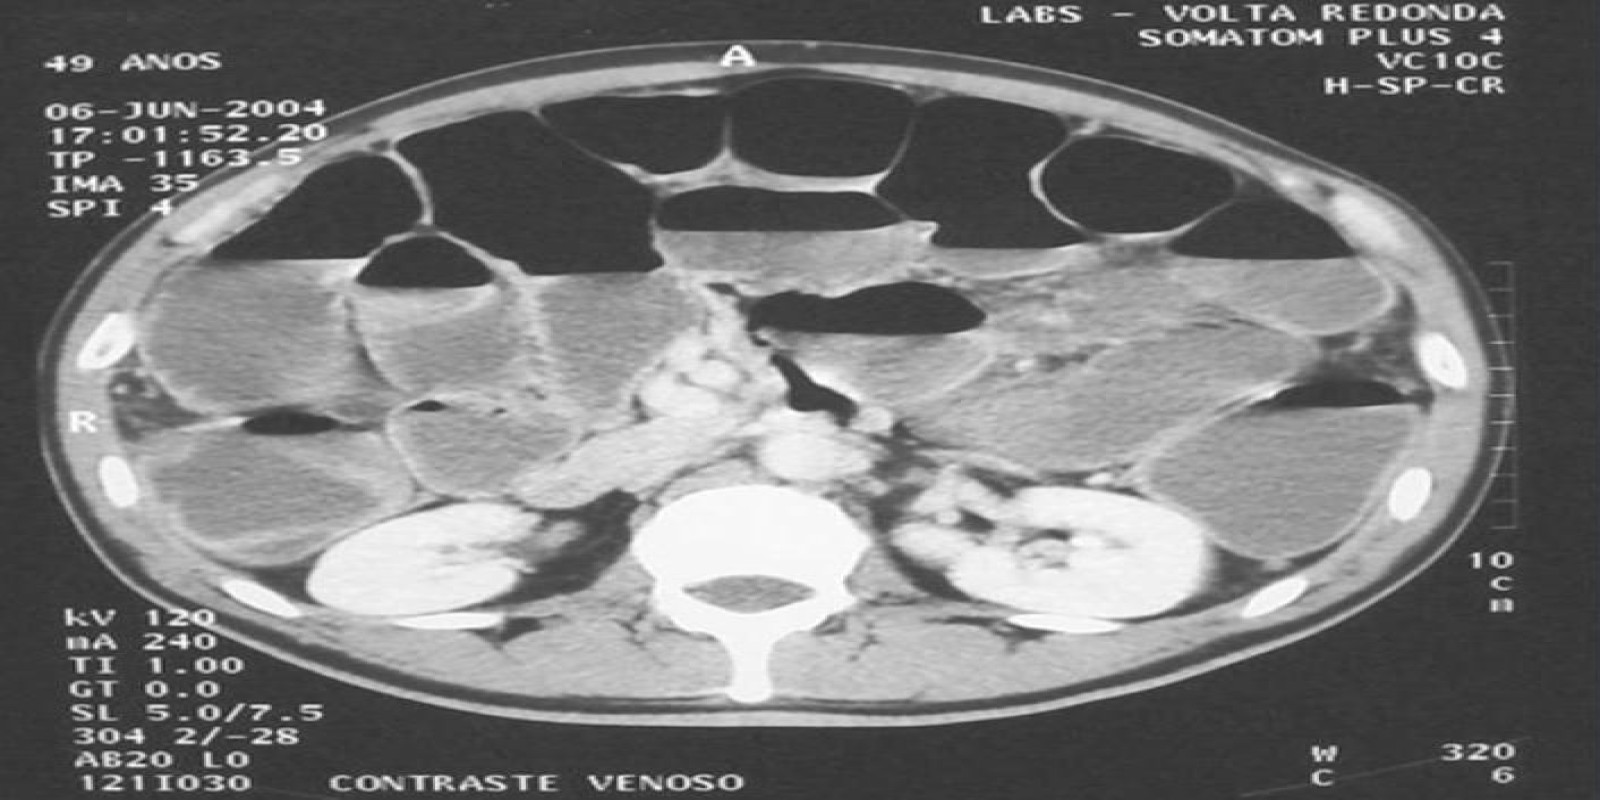

Caso Código 260A de Obstrução Intestinal do Cólon

Cod.: 260A